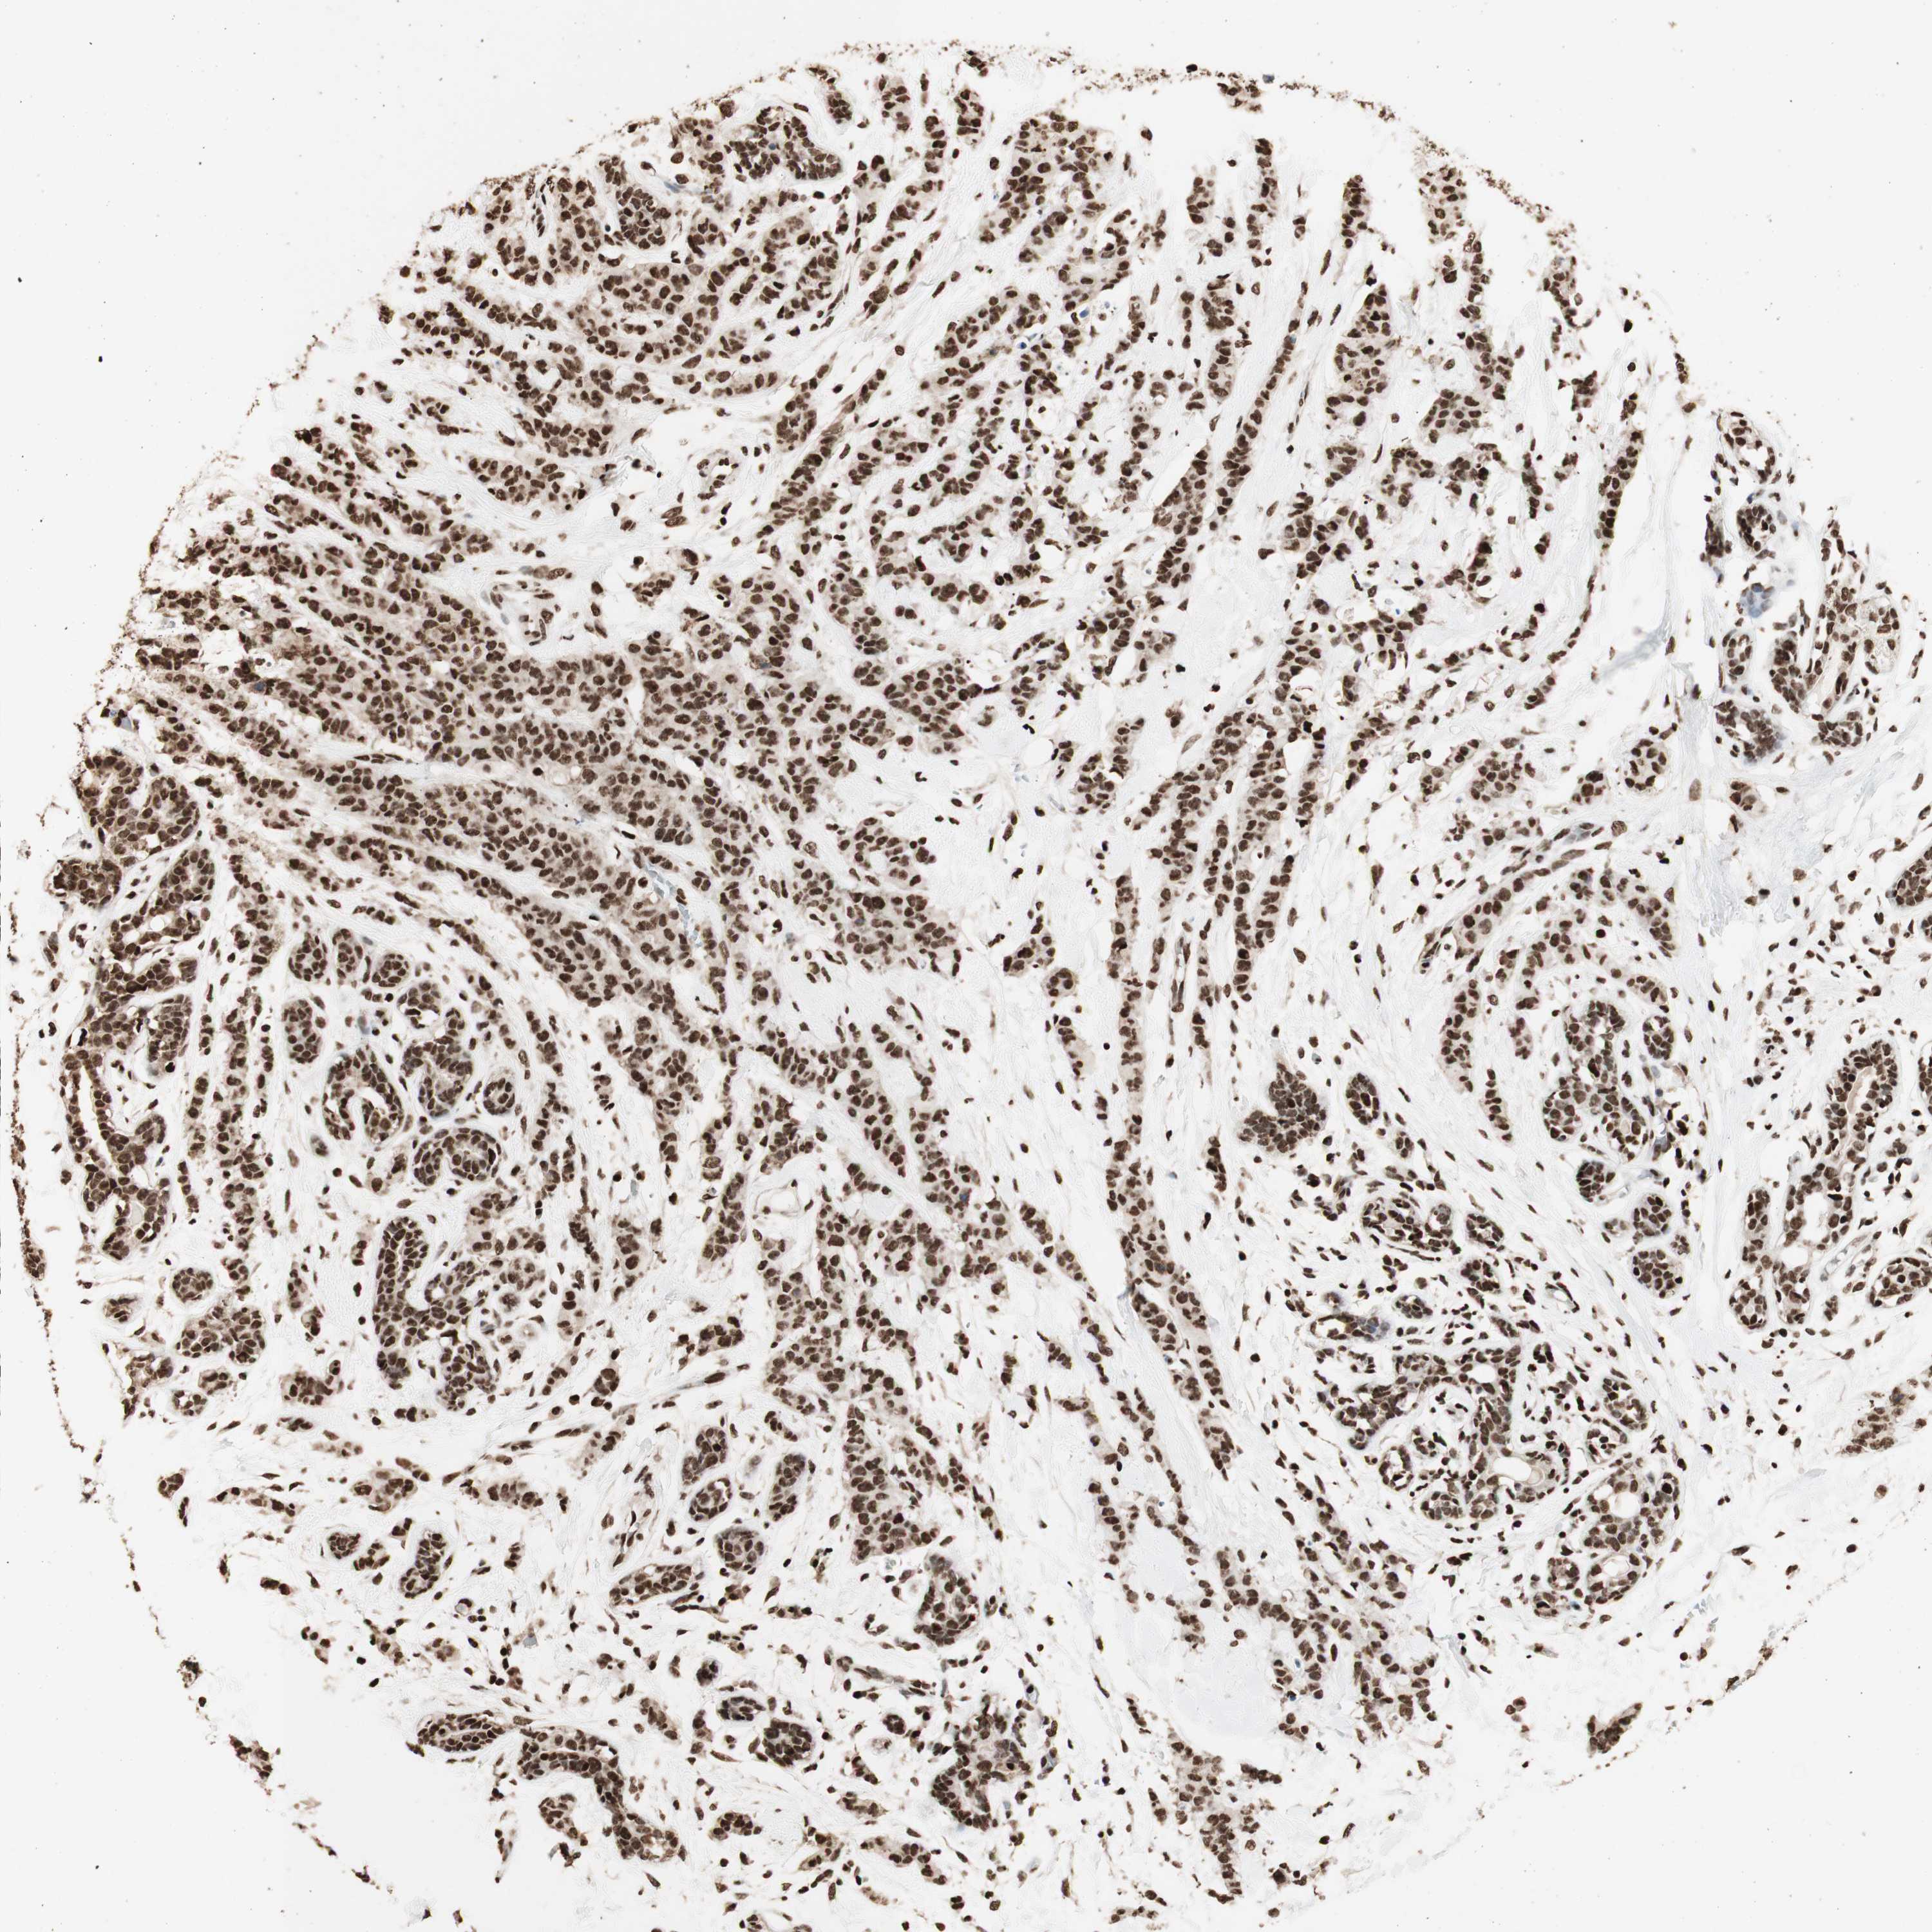

CANCER BREAST CANCER Show tissue menu

BRCA TCGA BRCA VALIDATION PROTEIN EXPRESSION